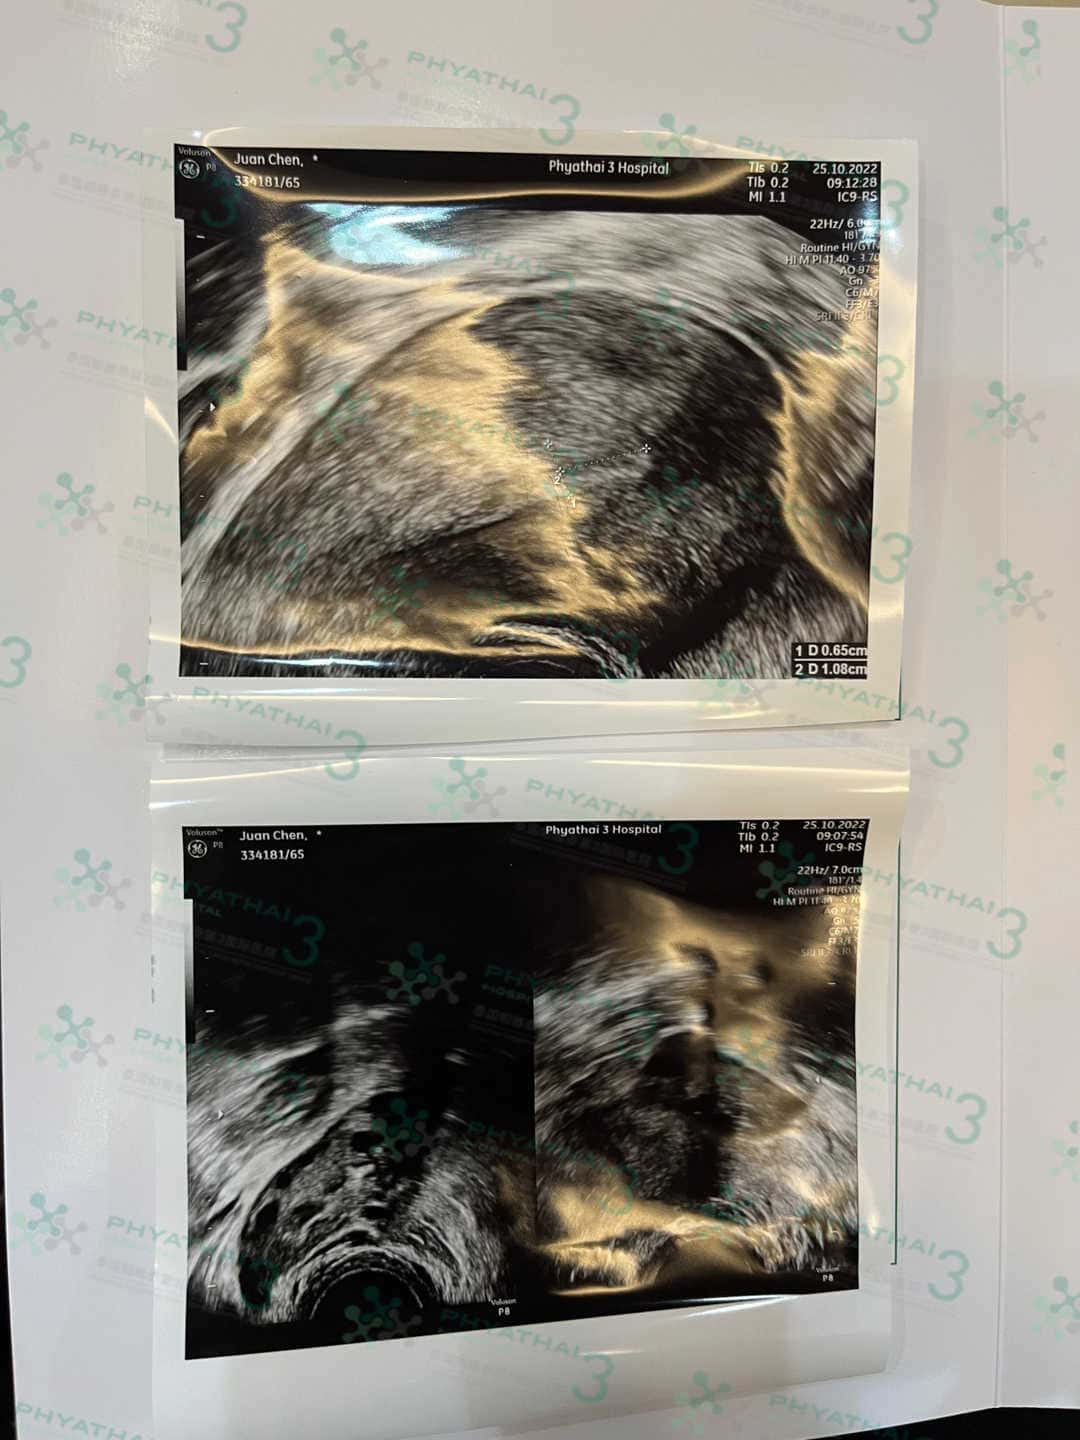

在移植前调理内膜最少要见医生2-3次见诊 每一次医生会给患者做阴超看内膜厚度 移植内膜厚度的话达标是8毫米以上 如果还没有达到医生会安排患者调理药 吃的、塞的 、涂的 也有贴的

或者我们叫内膜贴(CLIMARA) 患者经常问这是什么作用 其实内膜贴是针对子宫内膜薄增厚内膜吸收方式为透皮吸收的 贴一个星期一片 患者就会担心洗澡怎么办会掉吗? 这不用担心我们医院护士小姐姐会给我们患者准备好防水贴 而且如果当天就开始贴的话护士也可以帮患者贴好就不用担心贴不对地方了哦